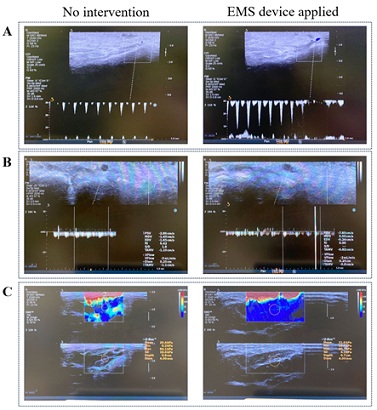

The comparison results of imaging assessments by using the EMS device and no intervention as shown in figure 2, the blood circulation of artery and vein are improved significantly (Figure 2(A) & 2(B)), and the muscle stiffness of lower limb is reduced after the EMS device applied. For artery circulation, the blood peak rate is around 20 cm/s by using the EMS device, but the peak rate is around 10 cm/s without intervention. Similarly for vein, the peak rate is around 7.8 cm/s with EMS device applied compared to 2.8 cm/s without intervention. Specifically, the blood circulation showed a marked improvement, indicating enhanced perfusion to the lower limb area. Additionally, the EMS device effectively reduced muscle stiffness, after this device applied, the mean intensity of pressure is around 21.6 kPa compared to 29.4 kPa before applying, that means the EMS device effectively reduced muscle stiffness, indicating its potential to alleviate muscular tension and promote relaxation.

Figure 2: Imaging assessment results by using EMS device and no intervention. A) Artery changes. B) Vein changes. C) Muscle stiffness changes.